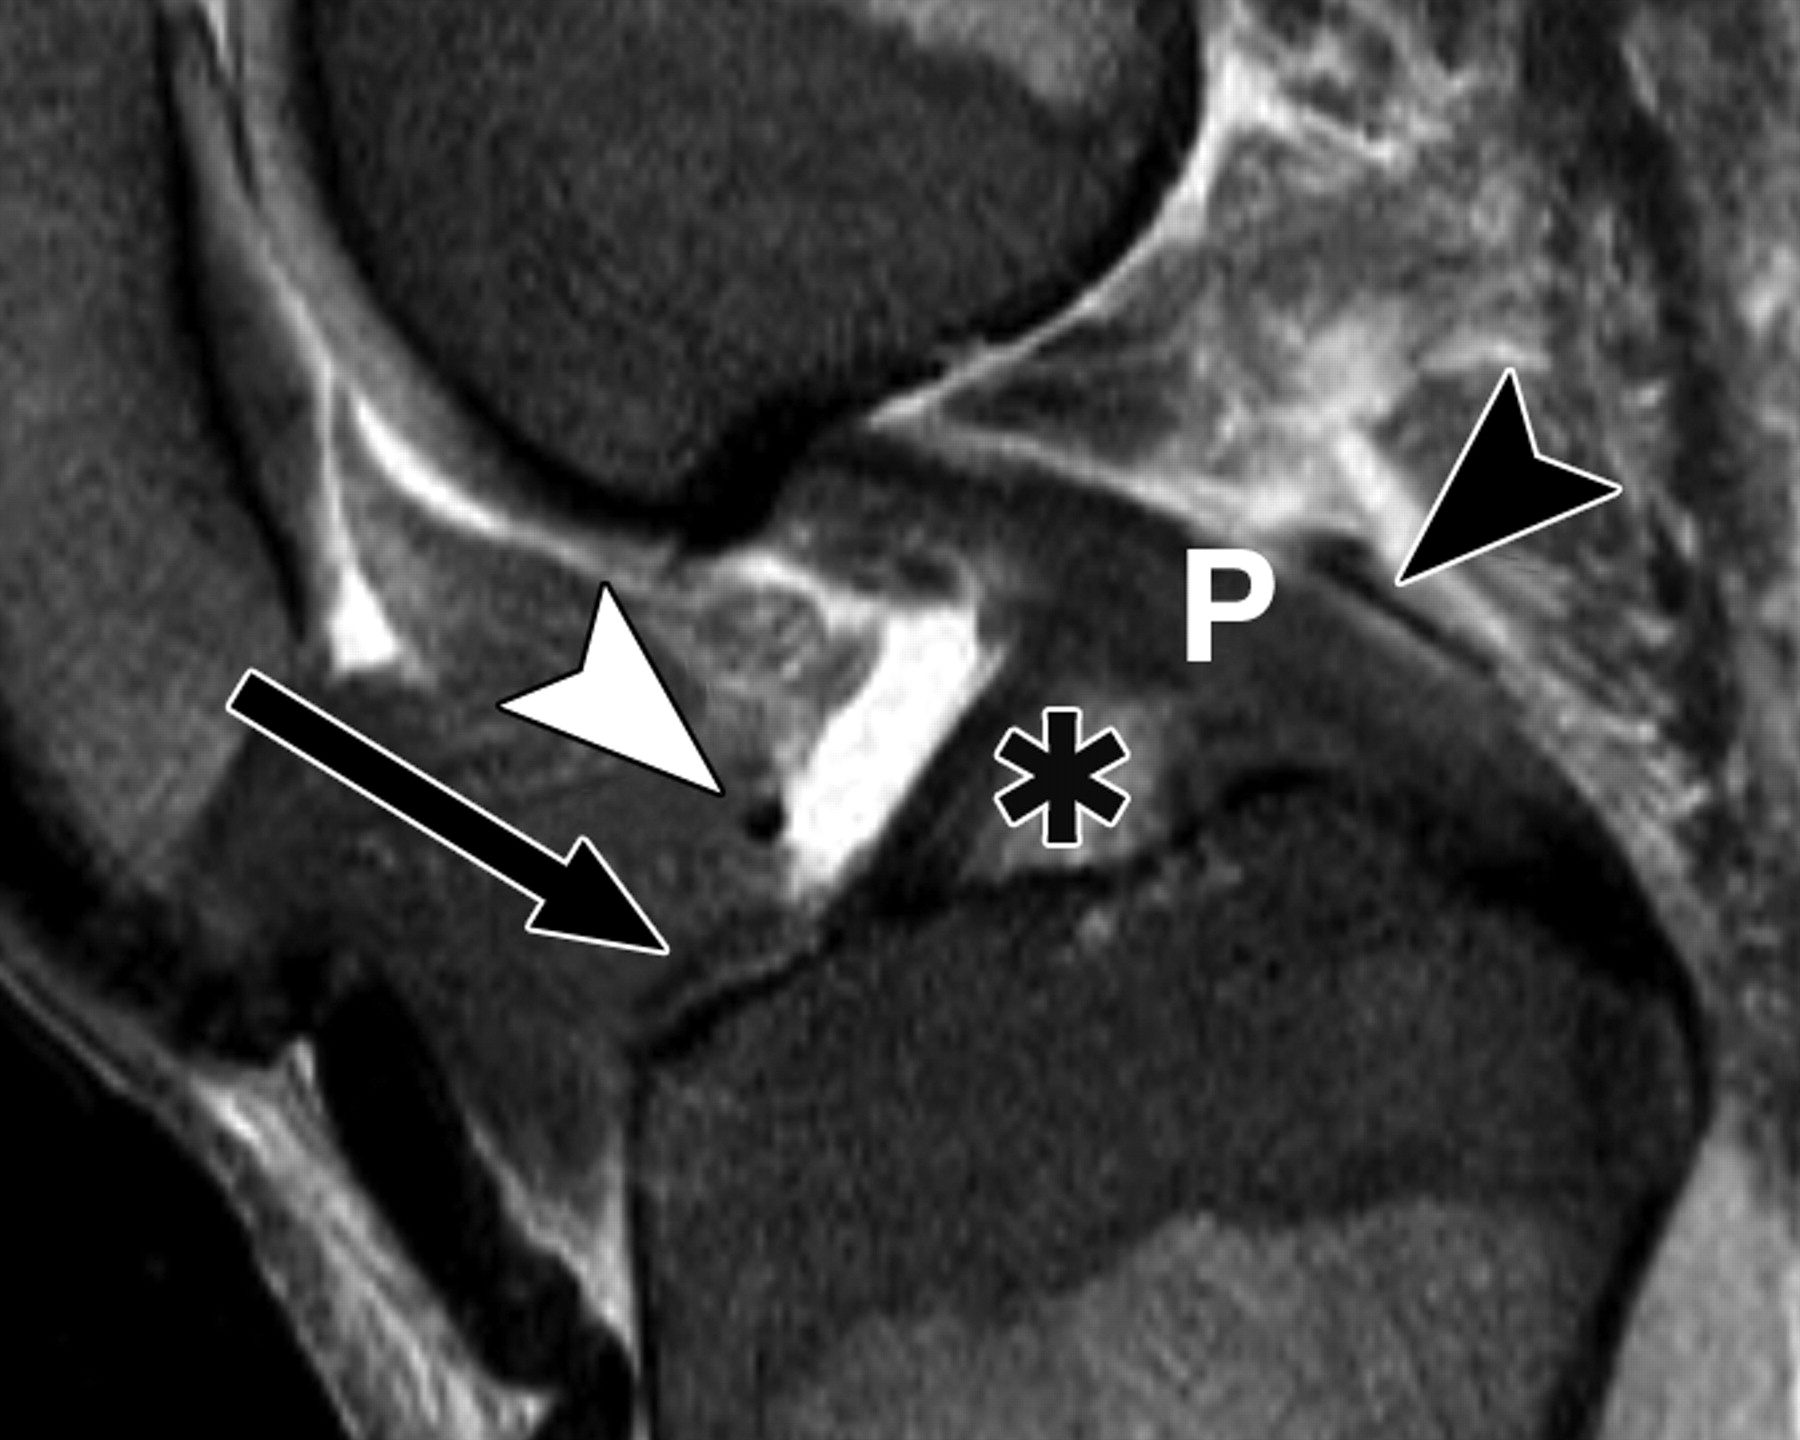

107f7f7cbccc5f7ef7f135a981bab0b2.jpeg

图5C-59岁男性,中等加权、脂肪饱和、快速自旋回波(TR/TE有效值,3,700/29)3-T MR图像显示半月板后根和交叉韧带的解剖关系。

冠状面图像依次位于A的腹侧,显示外侧半月板后根(LM)(白色箭头)和内侧半月板后根(MM)(黑色箭头,B)的插入,覆盖后髁间区域的一个以上切片厚度。MT =胫骨内侧结节。

56ddb74b91044972475ef5d11ebdf151.jpeg

图5D-59岁男性,中等加权、脂肪饱和、涡轮自旋回波(TR/TE eff,3,700/29)3-T MR图像显示半月板后根和交叉韧带的解剖关系。

通过后交叉韧带(P)的矢状图像显示内侧半月板后根的插入部位(箭头)相对于韧带插入部位位于前方。MT =胫骨内侧结节。箭头表示膝前韧带。